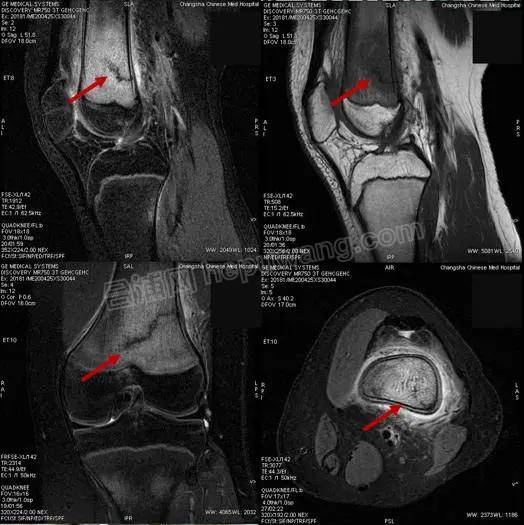

15岁的罗同学

因“右膝关节肿痛,加重1天”入院

在行膝关节磁共振成像检查时

发现“右侧股骨下段骨折并广泛骨髓水肿

通过仔细询问病史发现

这名疫情期间新近返校的初三学生

因临近中考需要参加体育考试

微信图片_20200503120407.jpg

每天都进行了

一定强度的体育训练

最近几天出现膝关节疼痛明显加重

于是家人带他到医院就诊

无独有偶,很快

又有三名同学陆续来院就诊

他们的情况与罗同学完全一样

都是14~15岁的初中生

在学校参加跑步等体育锻炼后

出现膝关节疼痛,并加重后就诊

经磁共振成像检查

被诊断为应力性骨折